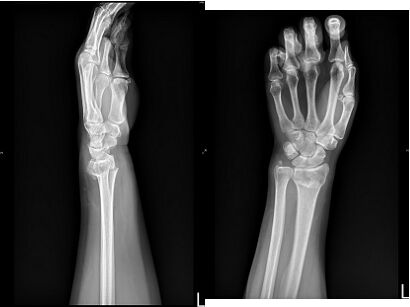

52.50歲女性昨日騎車摔倒後,左手疼痛腫脹變形瘀青明顯且無法用力,X光如附圖所示,今日就診, 下列敘述何者正確?(A)X光所示骨折處為左手遠端橈骨骨折合併尺骨莖突骨折(B)該骨折暴力機轉為跌倒時左手背先著地造成骨折(C)可依骨折分期用藥使用桂枝茯苓丸治療(D)該處骨折一般成人癒合時間為14週